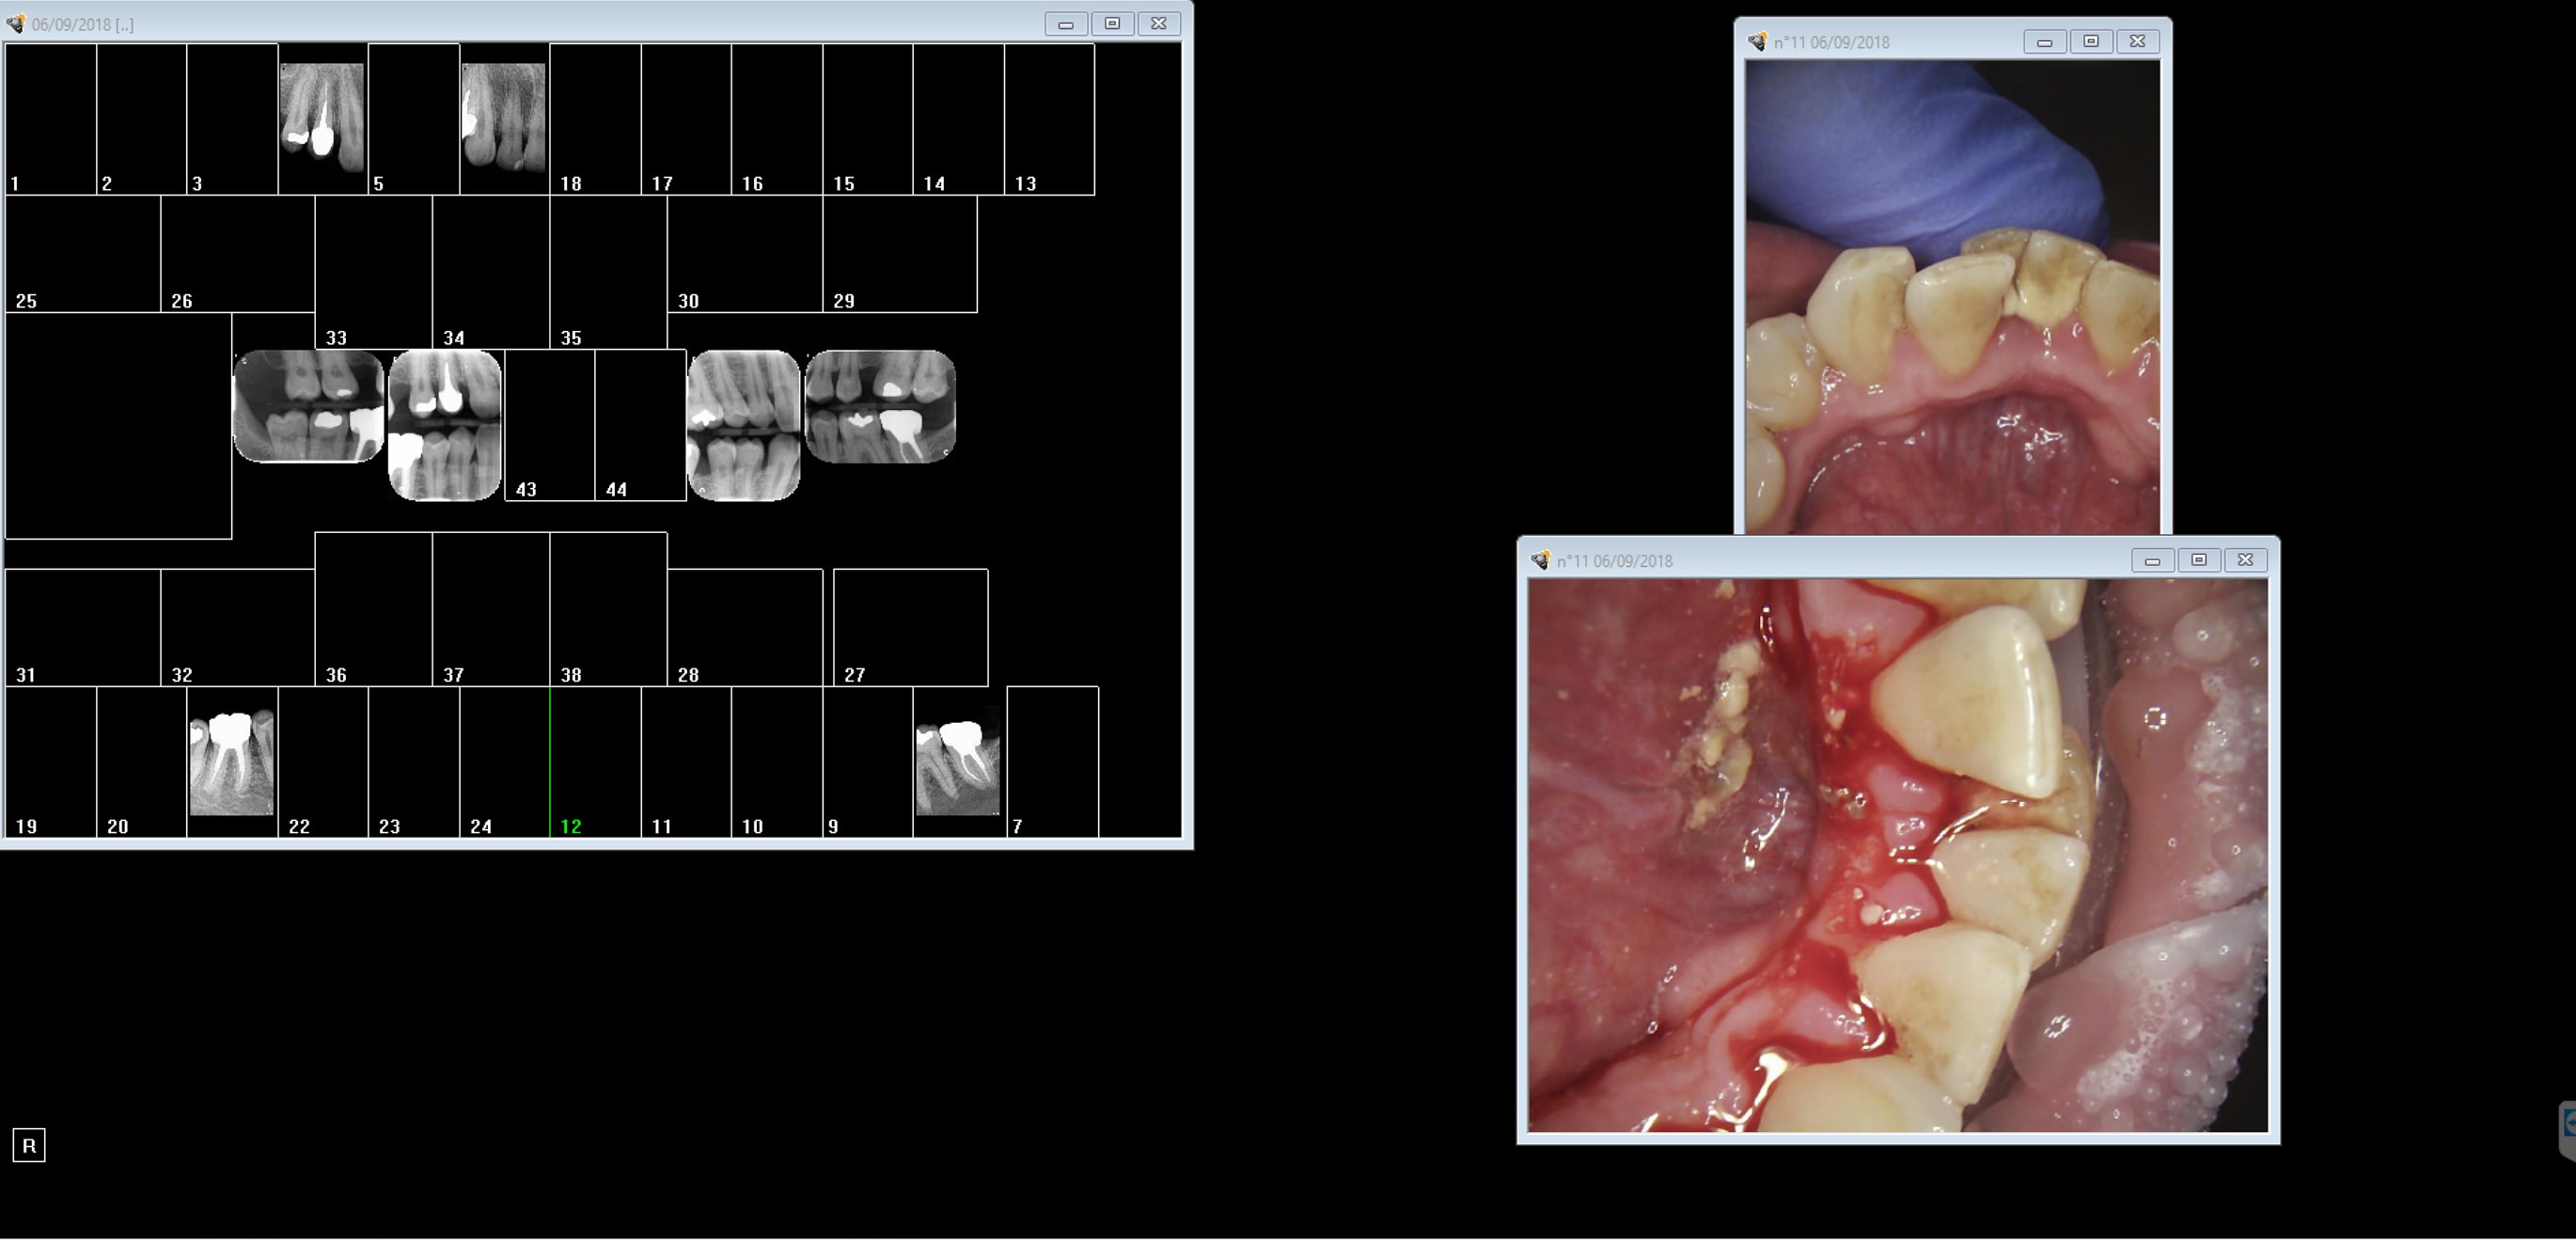

Capture d écran 2018 09 06 10.48 - Eugenol